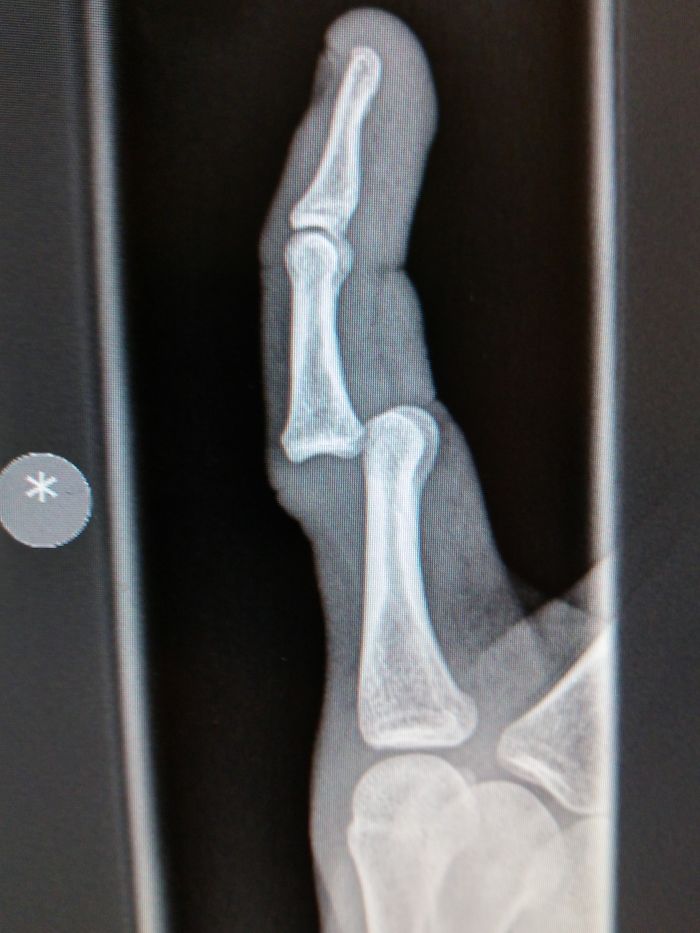

My Wife's A Ballerina, This Is Her X-Ray While En Pointe